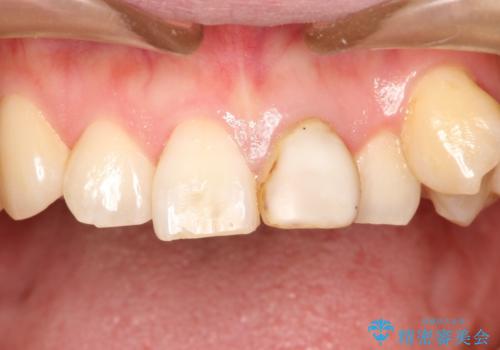

[前歯の変色] 前歯の見た目を改善したい

![[前歯の変色] 前歯の見た目を改善したいの症例 治療前](https://seimitsushinbi.jp/wp/wp-content/uploads/2021/05/510b0093313ff75fbcb626419a0f3045-500x350.jpg?v=1622180184)